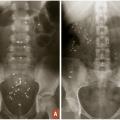

Temps de transit colique des marqueurs radio-opaques

Il s’agit d’un examen simple et reproductible permettant d’obtenir une mesure objective du temps de transit colique. Le temps de transit colique devra être réalisé sans prise concomitante de traitements laxatifs. Il consiste en l’ingestion par le patient pendant 6 jours consécutifs de marqueurs radio-opaques (10 marqueurs par jour) puis en la réalisation au 7e jour d’une radiographie de l’abdomen sans préparation. Le nombre de marqueurs résiduels présents sur le cliché d’abdomen sans préparation permettra de calculer le temps de transit, à la fois total et segmentaire (côlon droit, côlon transverse, côlon gauche et sigmoïde). Il pourra ainsi être distingué deux types de constipation, à savoir la constipation distale lorsqu’on objectivera une stagnation des marqueurs radio-­opaques au niveau du recto-sigmoïde (fig. 2A), ou la constipation dite de transit lorsque les marqueurs radio-opaques stagneront sur l’ensemble du cadre colique (fig. 2B). Le temps de transit global moyen est estimé à 67 heures en moyenne.